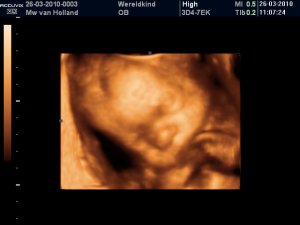

Zie hier ons nieuwste fotomodel! Jaja, in dit huishouden wordt je al op de gevoelige plaat vastgelegd voordat je geboren bent! Drie vaste onderdelen in dit huis zijn

Maar dit plaatje is van de pretecho, en is ie niet snoepig? Hij lijkt wel een beetje op Tom, maar of ie net zo makkelijk wordt na de geboorte is maar even afwachten..

Een lekkere dopneus zit erop en op andere foto's zijn ook al de reuzehandjes te zien (zie album). Tom had ook van die grote kolenschoppies en enorme drijvers als voeten toen ie geboren was. Deze lijkt dezelfde kant op te gaan. Wel raar, want mama heeft toch van poezelige afmetingen..hihi..

Bij andere pasgeboren babies kijken wij onze ogen altijd uit hoe klein handjes en voetjes blijkbaar kunnen zijn want die van ons zijn altijd qua grootte wel een jaartje verder!

Maar wat een liefie he?